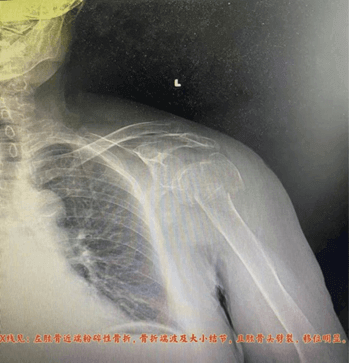

患者为85岁老年女性,因意外摔伤导致左肱骨近端粉碎性骨折。经影像检查,骨折程度严重(Neer分型四部分),肱骨头劈裂,大小结节均受累,移位明显,属极不稳定性骨折。